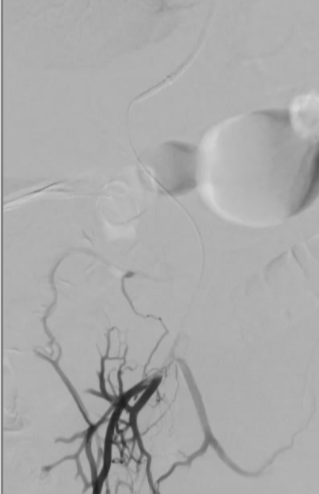

经右侧颈内静脉对肝内门静脉进行穿刺

将 VIATORR CX 型覆膜支架植入体内,以确保能够进入门静脉。 门静脉和肠系膜静脉的血栓清除术 肠系膜静脉中放置带有侧孔的溶栓导管,以处理残留的血栓物质